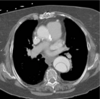

**Type B aortic dissection** - decending aorta